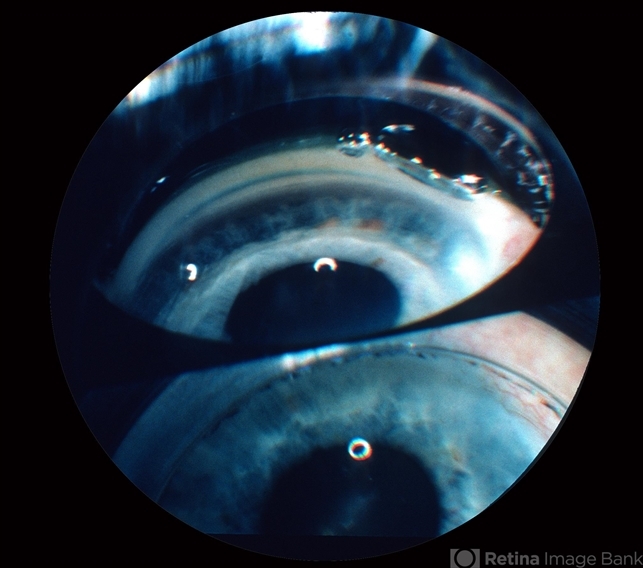

- gonioscopy, angle recession

- Angle recession, gonioscopy